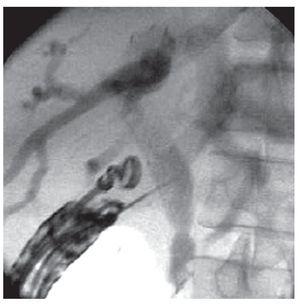

A 19-gauge FNA needle (Wilson-Cook Endoscopy, Winston-Salem, NC, USA) was used to perform a transduodenal puncture of the common bile duct through the proximal end of the biliary stent. Bile was aspirated and a cholangiogram demonstrated good filling of the right and left duct systems with no evidence of a stricture proximal to the puncture site (Figure 2). Under fluoroscopy, a 0.035-inch straight guidewire (Jagwire, Boston Scientific Corporation, Natick, MA, USA) was passed into the biliary tree and directed toward the hilum. Choledochoduodenostomy with a 10 mm x 60 mm partially covered self-expanding metal biliary stent (Wallfex®, Boston Scientific Corporation, Natick, MA, USA) was placed over the guide wire and deployed under fluoroscopy (Figure 3). Good bile and contrast efflux was seen (Figure 4).

¿ Figure 2. EUS guided puncture and cholangiogram demonstrating distal obstruction of the common bile duct.